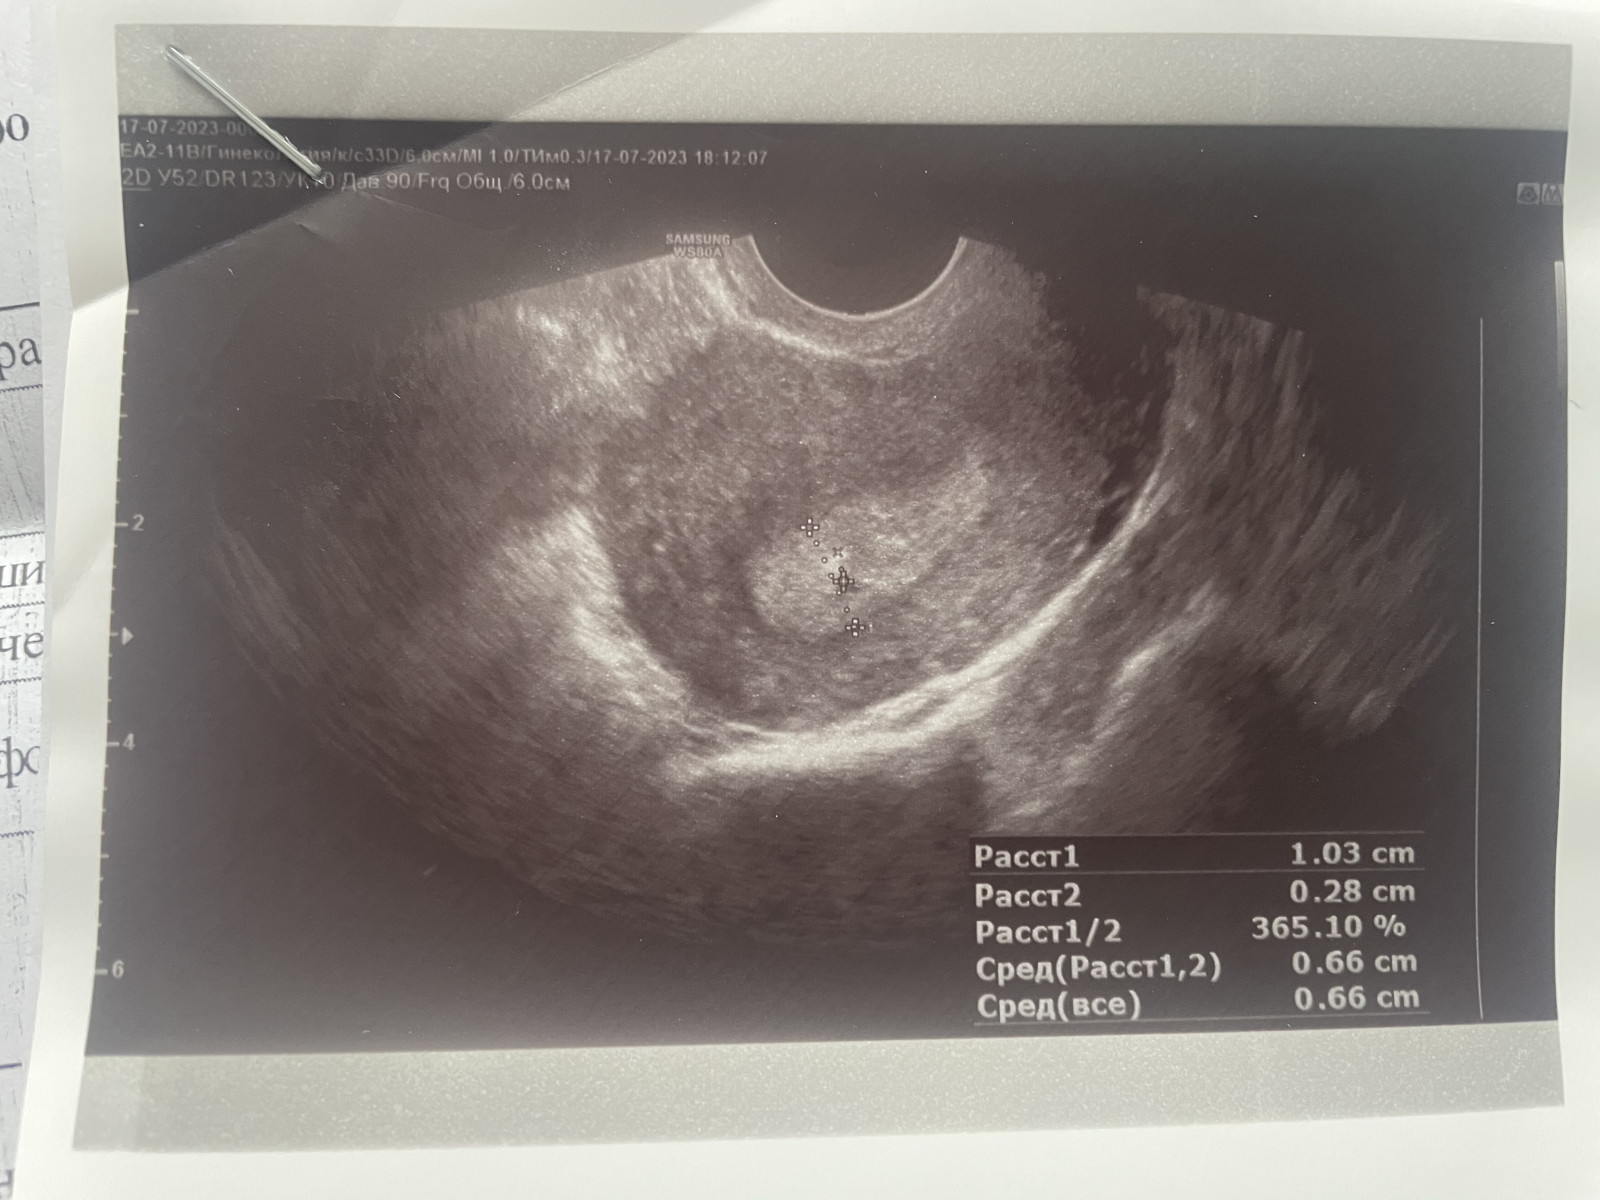

Эндометрия плоха растет

Эндометрия плоха растет 112 фотографий